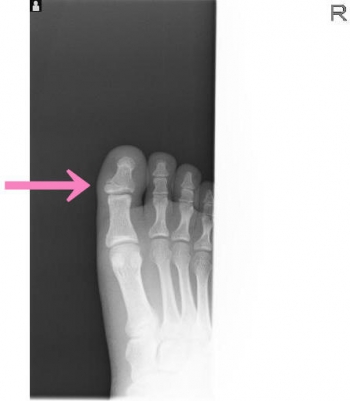

今日、ご紹介するのは、足・足指 足指骨骨折についてご紹介していきます。

足・足指 足指骨とは

足指骨は、四肢動物の後肢の先端部にある、足の指を構成する骨の集合です。

基節骨・中節骨・末節骨で構成される骨の集合で、動物の手足において、指に相当する部分を構成している。

手足の中心部分を構成する中手骨・中足骨とは基節骨が接し、中節骨、末節骨の順に繋がっています。

足指骨骨折

足指骨骨折の発生機序

直達外力では、重量物の落下が多い

介達外力では足尖から衝撃が加わり発生。

基節骨骨折、とくに第1、2指は足底凸の変形が残り、荷重および歩行障害が起こりやすいです。